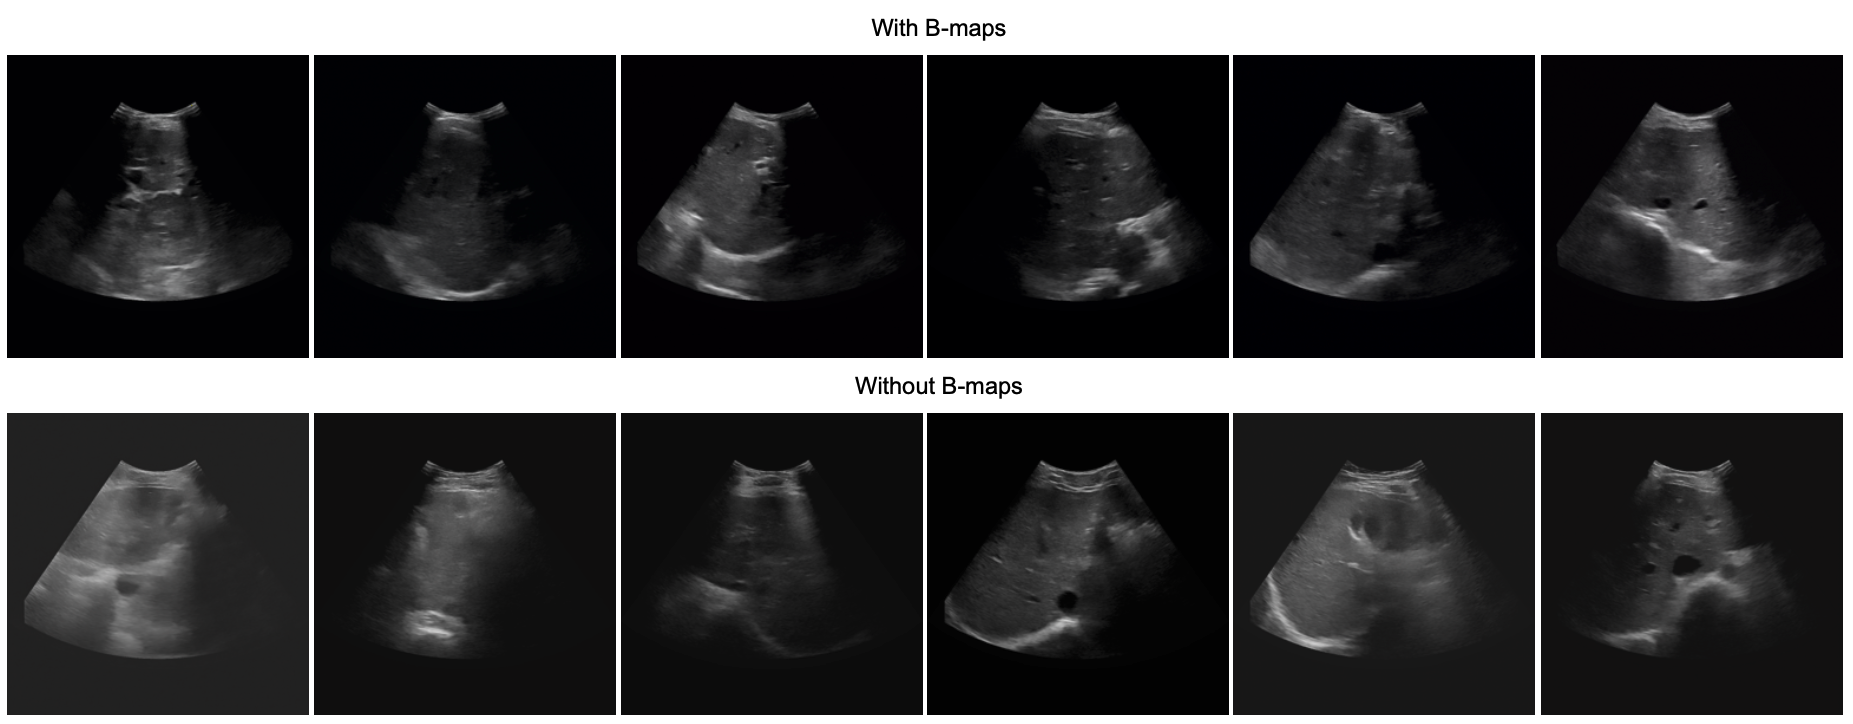

Qualitative Analysis: Visually, the integration of B-Maps has demonstrated a notable improvement in the synthetic images generated using both SDM and Guided-Diff. Figure 4 showcases examples from each dataset, illustrating the improvement in image quality and realism, especially in terms of contrast in the upper regions of the images, aligning with the known characteristics of US scans. Additional visual comparisons are available in supplementary material (Sec.Supplementary Material).

Refer to caption

Figure 4: Qualitative comparison: The top row displays the label maps used for SegThy and CAMUS datasets. For the liver dataset, no labels were used. The bottom row shows the US images generated with B-Maps (left) versus without B-Maps (right) for each dataset.

Figure 5: Liver Results: US images generated with B-Maps (top) exhibit enhanced contrast, especially in the upper regions, compared to those without (bottom).

Figure 6: Thyroid Results: The application of B-Maps in the generation of thyroid US images (top row) results in a clearer delineation and contrast, which is less pronounced in images generated without B-Maps (bottom row).

Figure 7: CAMUS Results: Images generated with B-Maps (top row) have improved contrast in the superior sections, contrasting with the lower contrast seen in the images without B-Maps (bottom row).